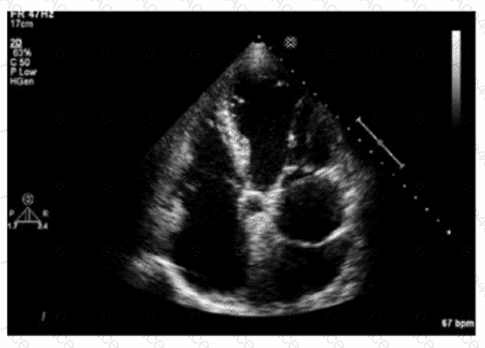

The echocardiographic image shows a mobile, highly echogenic, mesh-like structure within the right atrium consistent with the Chiari network. The Chiari network is an embryologic remnant of the right valve of the sinus venosus, appearing as a fenestrated, reticulated membrane that is usually thin and mobile, found near the orifice of the inferior vena cava or the coronary sinus.

This structure is benign and often an incidental finding but can be confused with thrombus or atrial tumors. Unlike left atrial thrombus, which appears as a more solid, immobile mass often located in the left atrial appendage, the Chiari network is mobile and located in the right atrium. Cor triatriatum is a rare congenital membrane dividing the left atrium into two chambers and appears differently on echocardiography. Artifact refers to non-anatomic echoes which do not persist or move consistently.

Recognition of Chiari network is important to avoid misdiagnosis, and its characteristics are well described in echocardiography literature such as the "Textbook of Clinical Echocardiography" and ASE imaging guidelines【16:Textbook of Clinical Echocardiography, 6e†p.400-402】【12:ASE Guidelines on Cardiac Masses†p.150-155】.